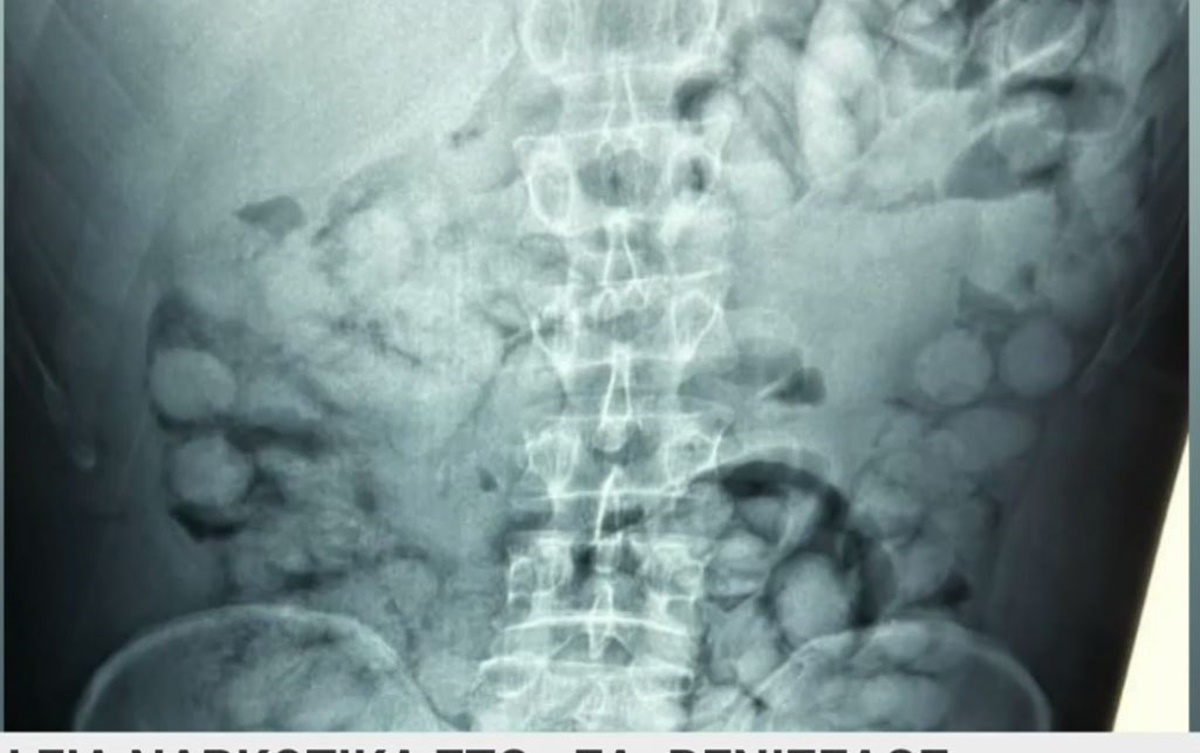

Σύμφωνα με τη δήλωση της ΕΛΑΣ, ο άνδρας έφτασε στην Αθήνα μέσω Παρισιού και, κατά τη διάρκεια του ελέγχου στο αεροδρόμιο, αποκαλύφθηκε ότι είχε μέσα του περίπου 100 συσκευασίες κοκαΐνης. Οι αρχές διαπίστωσαν την ύπαρξη των ναρκωτικών μέσω ειδικών τεχνικών διάγνωσης, που εφαρμόζονται σε ύποπτους επιβάτες διεθνών πτήσεων. Η ΕΛΑΣ υπογράμμισε τη σοβαρότητα της υπόθεσης, σημειώνοντας ότι οι δράσεις αυτής της φύσης αποτελούν άμεση απειλή για τη δημόσια ασφάλεια και υγεία. Οι έρευνες συνεχίζονται για να διαπιστωθούν οι διασυνδέσεις του συλληφθέντα και να εντοπιστούν οι υπεύθυνοι του κυκλώματος διακίνησης.